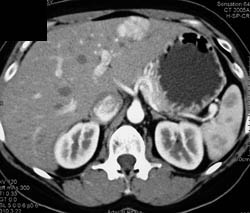

Liver Metastases